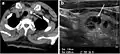

Nodules in skin include dermatofibroma[5] and pyogenic granuloma.[6] Nodules may form on tendons and muscles in response to injury,[7] and are frequently found on vocal cords.[8] They may occur in organs such as the lung,[9] or thyroid,[10] or be a sign in other medical conditions such as rheumatoid arthritis.[11]

Often discovered unintentionally on a chest x-ray, a single nodule in the lung requires assessment to exclude cancer.[9]